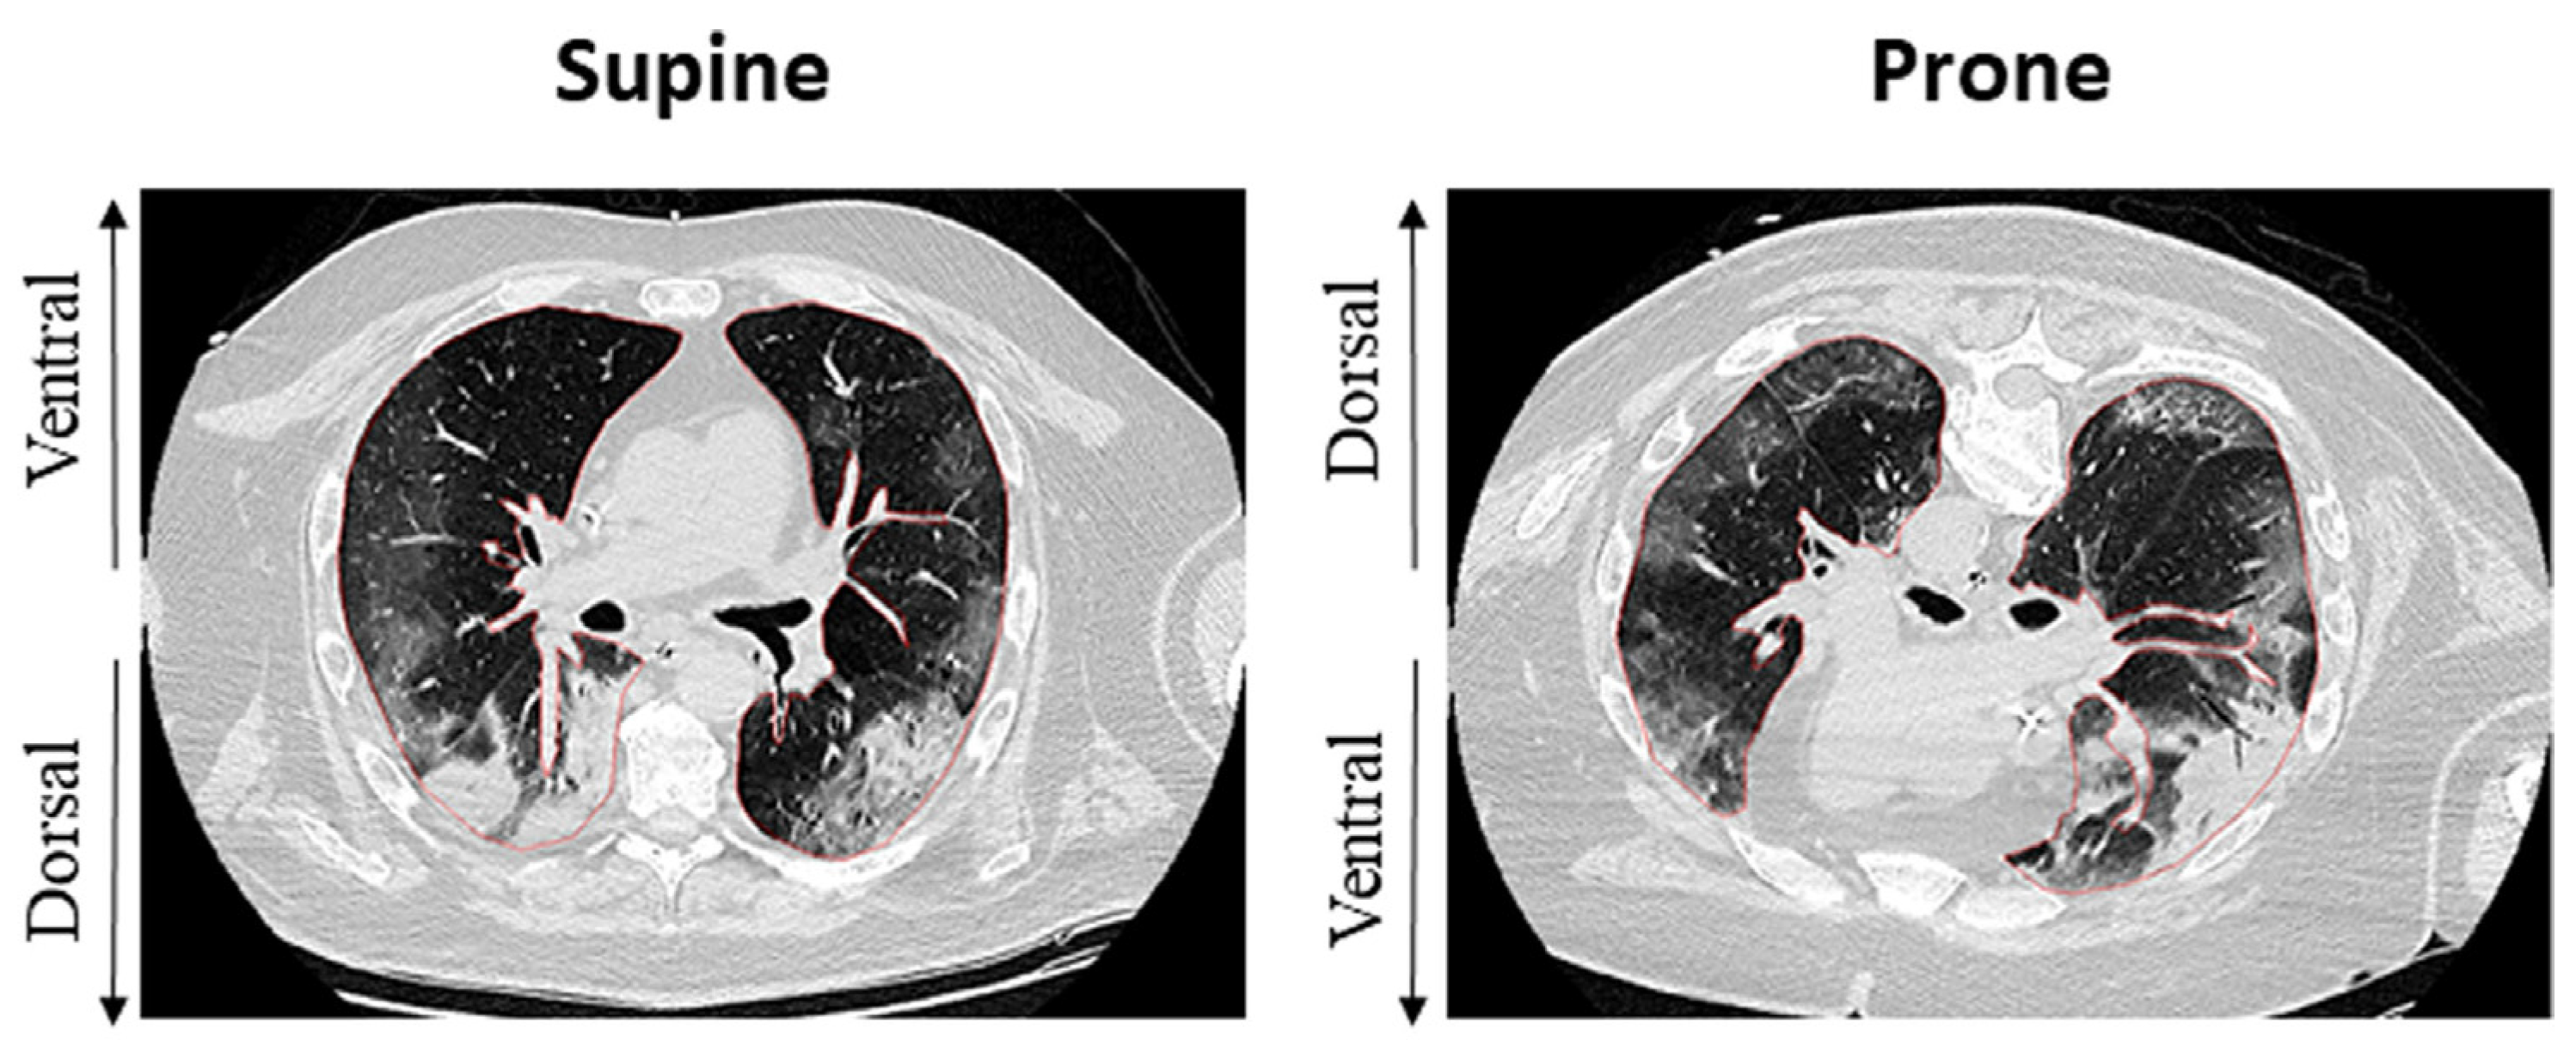

Improvement in gas exchange, as reported by the PaO2 increase, was the first therapeutic benefit described for the prone position [1]. The PaO2/FiO2 ratio continues to be a pivotal criterion in the starting prone position [9,30]. However, increased alveolar oxygen diffusion may be the result of several macro- and microscopic physiological modifications that the lung parenchyma undergoes during prone positioning [31]. Optimization of ventilatory/perfusion matching (V/Q ratio) and reduction of intrapulmonary shunt represent key elements of the process [32,33] (Figure 1).

Figure 1.

Changes in V/Q ratio after initiation of PP in mechanically ventilated patients with ARDS. Redistribution of ventilation more homogeneously helps the overall reduction of V/Q mismatch. See the text for details.

In the supine position, gravity impacts the distribution of inflammatory edema, increasing its content in the dependent regions and redistributing ventilation preferentially to non-dependent areas, where transpulmonary pressure is lower and the ventral rib cage has greater compliance [30].

These macroscopic modifications ultimately lead to dorsal collapse, which is evident on CT imaging of ARDS [38,39]. (Figure 2) Lung protective ventilation strategies with lower tidal volume and a moderate-to-high PEEP level demonstrated significant benefit in this setting [40]. However, in patients with moderate-severe ARDS, disease progression makes lung protective ventilation insufficient, requiring damaging pressures to maintain sufficient gas exchange, possibly meeting the criteria for starting in the prone position.

Figure 2.

Effects of the prone position on recruitment and ventilation distribution in a patient with C-ARDS. Inhomogeneity of dorsal regions appears reduced after shift to PP, whereas ventral regions appear less recruited, possibly by means of reduced overdistention. Adapted from Fossali T. et al. [41].

In the prone position, the inversion of the ventral and dorsal lungs redistributes the mechanical characteristics of the chest wall, decreasing its overall compliance [29] and changing its interaction with the lungs. Inversion of gravitational forces on parenchyma has been demonstrated on CT studies [30], and cardiac compression on lung parenchyma is also released. Changes in respiratory system compliance depend not only on the opening of previously unrecruited parenchyma but also on the improved mechanical behavior of already-opened alveoli [39,42]. When these changes occur together, the respiratory system moves towards a more favorable position, and total stress and strain may redistribute more homogeneously [36]. The reduction of airway plateau pressure after prone positioning thus acts as an indirect indicator of improved respiratory system compliance [42]. Pleural pressures also show a more homogeneous gravitational gradient in the prone position than in the supine position, possibly as a result of regional improvements in ventilation distribution [42,43]. Conversely, perfusion distribution does not change considerably in the prone position. The dorsal parenchyma still receives most of the blood flow even when turning to the non-dependent position, with a limited contribution from gravity [31,44].